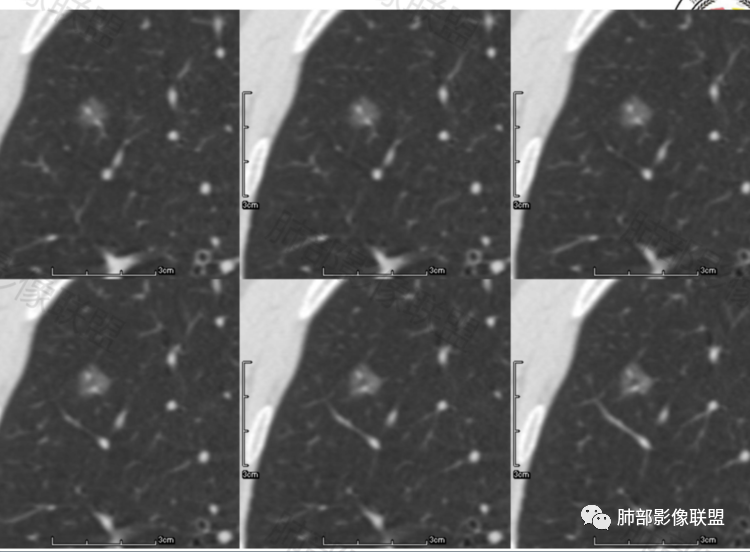

病历二:左肺磨玻璃结节影,边界清楚,内部血管穿行,考虑炎性结节或良性结节,继续短期随访。

病例二老年女性,左肺上叶纯磨玻璃结节,边缘清楚,有月牙铲?内部有稍高密度影,血管增粗,考虑微浸润癌MIA,建议密切随访,一个月复查。

第一例纯磨玻璃结节,边界清,其内可见空泡,血管被拉直增粗,考虑MIA。病例二混合磨玻璃结节,边界清,血管贴边,考虑炎性病变,抗炎后复查,排除MIA。

2例磨玻璃结节,复查无吸收,增大约2mm,说明增大不明显,病例2月牙铲,病例1首先考虑AIS,继续追观复查;病例2考虑MIA

晨读,病例1,磨玻璃影,边界清楚,血管穿行,内空泡,考虑微浸润。病例2,磨玻璃结节,边界清楚,月牙铲,血管穿行,考虑腺癌。

病例2:中年女性患者,左肺上叶磨玻璃结节,边界清晰,有月牙铲改变,内部有增粗血管走形,1年后复查略有增大,考虑原位或微浸润

病例二:中年女性,左上肺亚实性GGO,纯ggo为主,局部见少些条片状高密度实性区,,边界清,有分叶和月牙铲,血管从边缘穿过,14个月后稍有增大,考虑MIA可能,建议手术。